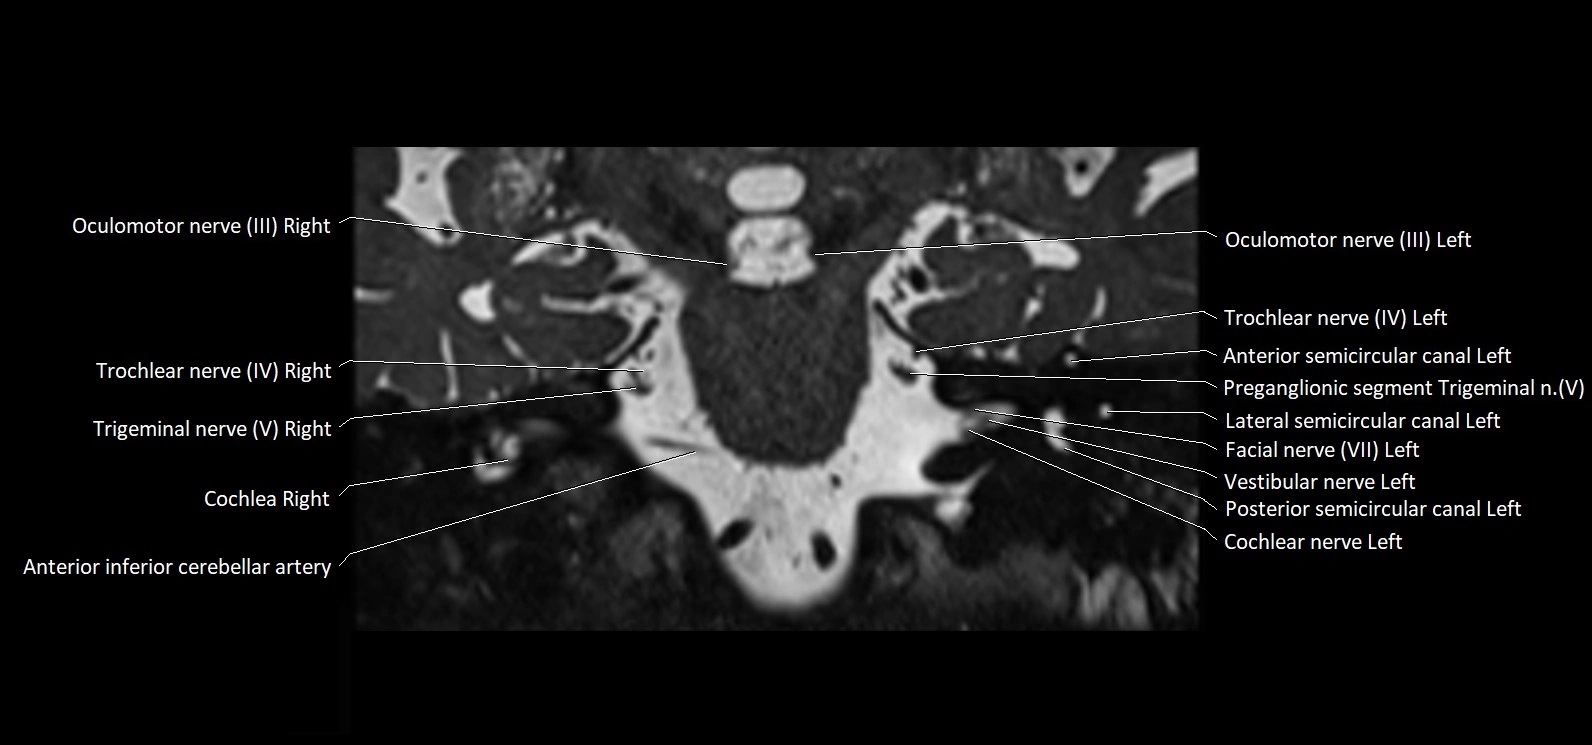

MRI images

image